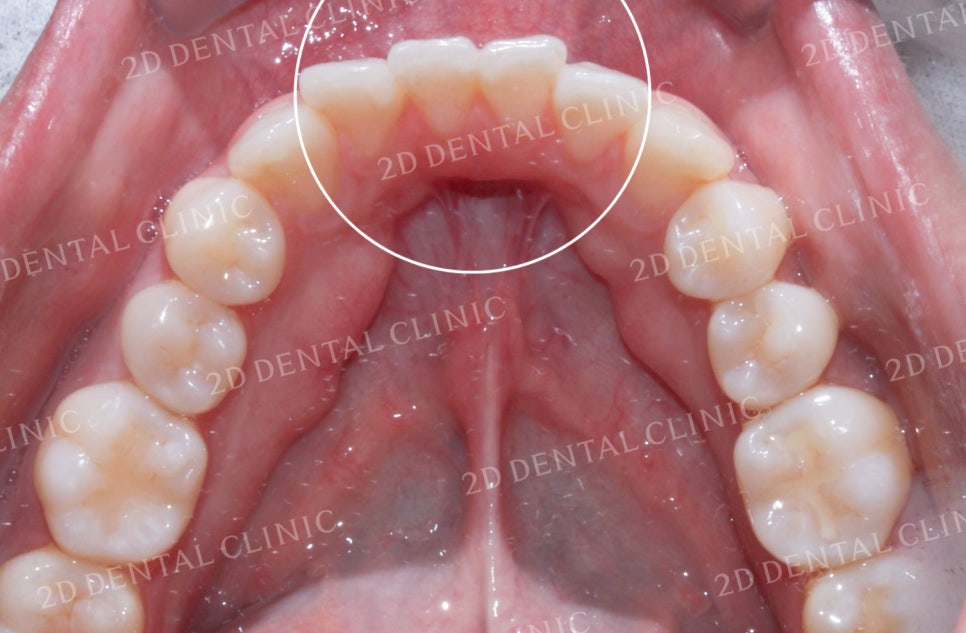

<하악 설측면 사진> <상악 설측면 사진>

상악과 하악의 설측면 사진입니다.

하악의 경우 전치부의 좁은 공간으로 인해

총생이 발견되는데요,

상악 역시 치아가 올바르게 배열되기에

충분한 공간이 확보되지 못한 상태입니다.